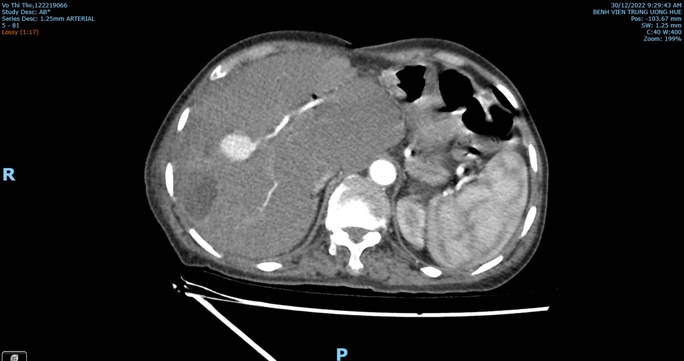

Bà Th. nhập viện vào cuối tháng 12-2022 với tình trạng sốt cao, đau hạ sườn phải. Kết quả CT Scan bụng cho thấy hình ảnh áp-xe gan và khối giả phình động mạch ở gan phải.

Kết quả chụp CT Scan bụng lại, nội soi kiểm tra tính chất mật chảy qua bóng Vater khẳng định được bệnh nhân bị vỡ giả phình động mạch gan nên được hồi sức tích cực, can thiệp nút động mạch gan chọn lọc qua da cấp cứu thành công.